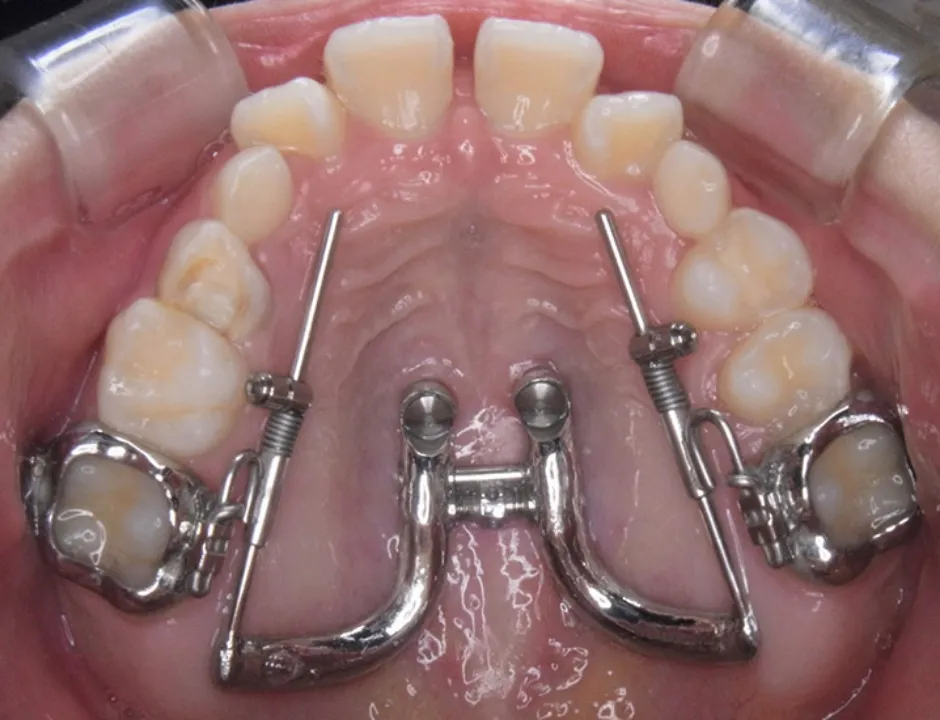

MSE(上顎骨骨格性拡大装置)は、矯正用アンカースクリューを使って上顎の骨を横に拡大する装置です。上顎の骨は左右に分かれており、その真ん中に正中口蓋縫合とよばれる骨のつなぎ目があります。MSEは、この骨のつなぎ目の右と左にそれぞれ2本ずつ、計4本のアンカースクリューを埋め込んで固定します。これによって左右の骨が少しずつ引き離され、その間に新しい骨が形成されることで、上顎の骨を横へと拡大できます。

具体的には、3Dスキャナーを使用して、アンカースクリューのヘッド部、上顎の天井の粘膜、歯の3次元的な位置関係をデータとして取得し、そのデータを基にCAD/CAM技術を駆使して矯正装置を設計・製作します。この3Dメタルプリント矯正装置は、歯への適合性と強度に優れており、幅広い症例に対応が可能です。

デジタル技術の進歩により、現在では3Dスキャナーで取得した患者様の口内の3Dデータを基に、CAD/CAM技術を活用して矯正装置の設計から作製まで行なうことが可能です。矯正用アンカースクリューと連結できる矯正装置も、3Dメタルプリント技術を用いて、患者様一人ひとりに合わせて精密に設計・製作することにより、対応可能な症例の幅が広がっています。